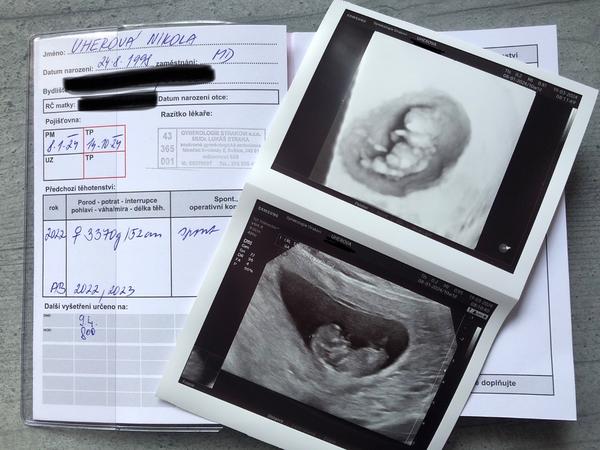

@aquenka tak holky, už mám po kontrole a to maličké pěkně roste dnes 10+1tt, malé odpovídá 10+0tt ❤️ a měří 3,2cm 🥹 na prvni screening jsem objednaná 9.4☺️